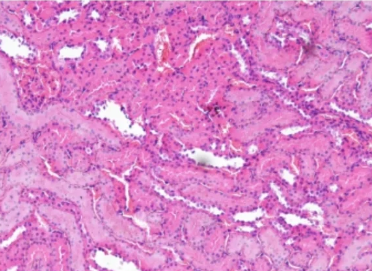

HE染色适用于生物医学、病理学科研与教学。在病理诊断中,HE染色是病理诊断上较广泛采用的常规染色方法,通过染色可以让组织在显微镜下显示得更清楚,有助于辅助做出正确的病理诊断。

一、染色不均

染色不均